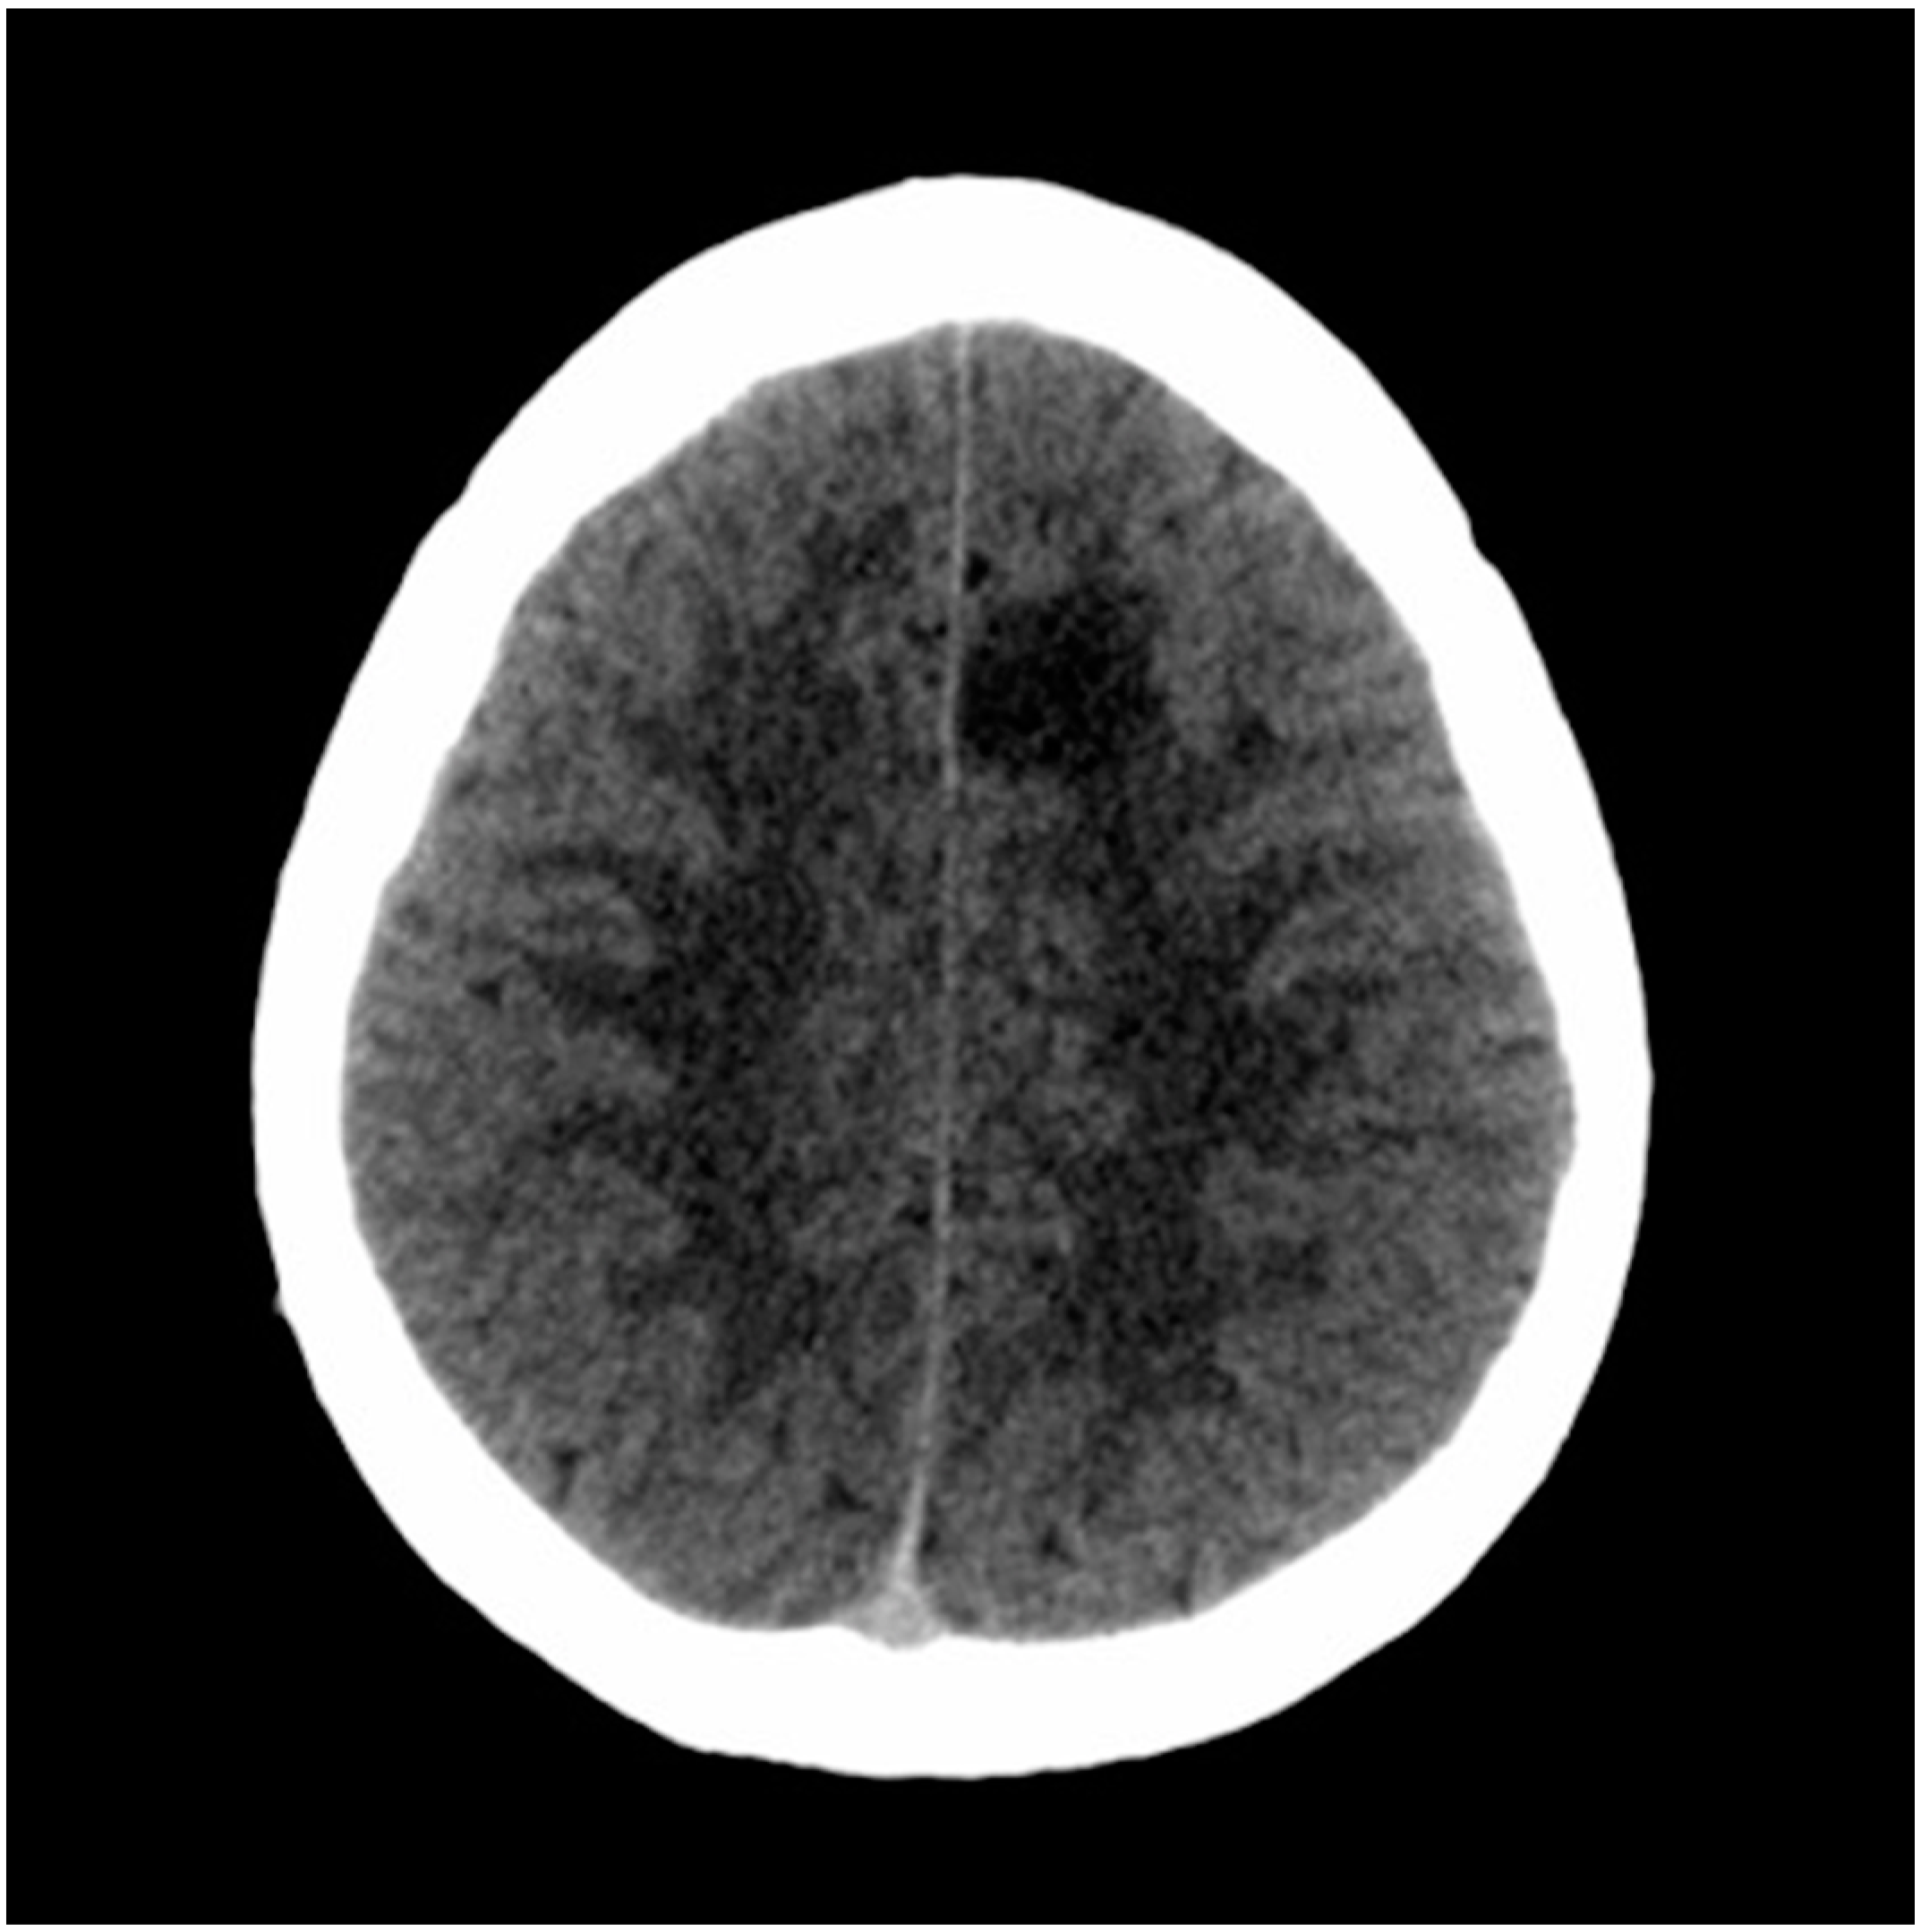

After consulting the emergency room for these symptoms, he was discharged due to “muscle weakness after physical exercise”. As the hours passed, he reported an improvement in the weakness, although with persistent right brachiocrural paresthesia, as well as manipulative clumsiness of the right hand and a feeling of dullness in the head. Finally, given the persistence of symptoms, he decided to return to the emergency department and was then assessed by the on-call neurologist. The vital signs were blood pressure 128/68 mmHg, heart rate 82 bpm, oxygen saturation 100% and temperature 36.0 °C. Neurological examination showed the following: alert and oriented; language, speech and voice were preserved; normal cranial nerves; motor balance preserved; right Babinski’s sign; preserved exteroceptive sensitivity; coordination without dysmetria; and cautious gait, not ataxic. A computed tomography (CT) scan of the brain was urgently requested (Figure 1), showing findings compatible with a subacute ischemic lesion in the territory of the left anterior cerebral artery.

Figure 1.

Computed tomography scan of the brain. The hypodense lesion in the medial left frontal lobe could be compatible, among other possibilities, with subacute ischemic stroke in the vascular territory of the left anterior cerebral artery.